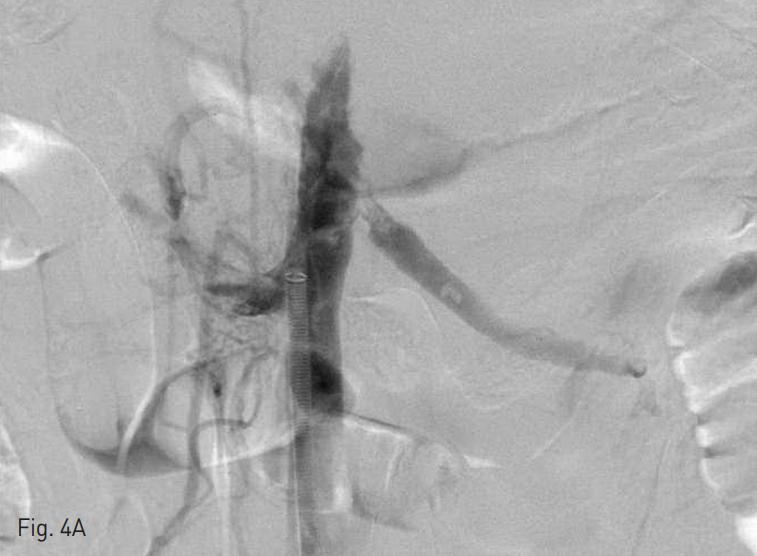

Fig. 4

A. Follow up venography after overnight thrombolysis shows Remnant thrombosis in infrahepatic IVC.

B. Aspiration thrombectomy was performed again.